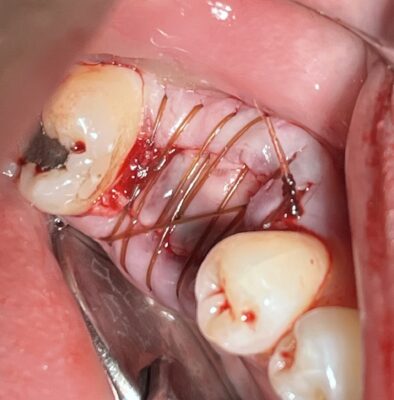

Jedediah posted an update a year ago

OK Dojo Peeps. Some of you wanted to see some suturing techniques for socket preservations that we went over during the last study club meeting so here you go. Lots of different ways that you can do it. A lot of it just comes down to preference. This one is an inverted figure 8 with multiple passes. I find this to be a very useful…